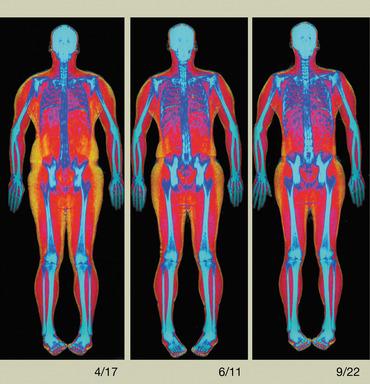

Incomplete Atypical Femur Fractures imaged with a Hologic densitometer, courtesy of Prof. Cheung, University of Toronto.

- A Single-Energy Femur Exam that allows clinicians to visualize potential atypical femur fractures, an unusual form of femur fracture which can occur as the result of bisphosphonate use;

- Advanced Body Composition assessment with visceral fat estimation to assist in the evaluation of metabolic health.